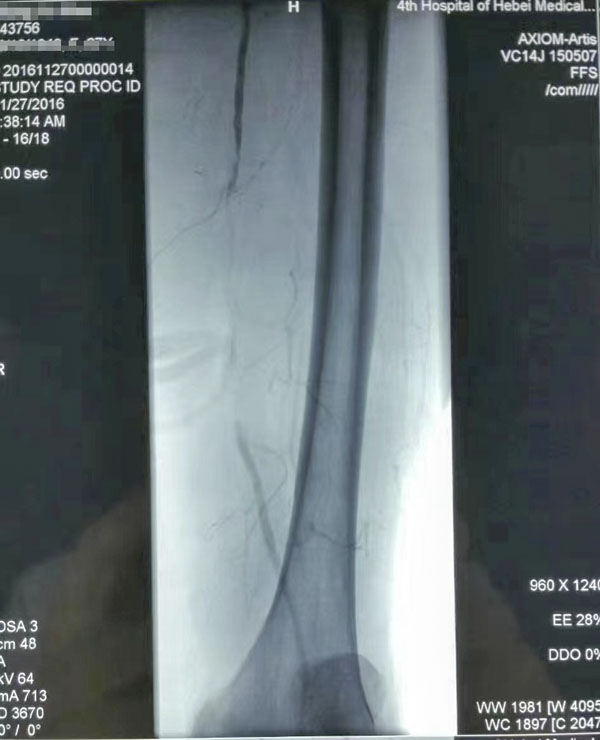

介入治療前后對比

糖尿病足重在預防,而預防和治療下肢血管病變是防治糖尿病足的有效措施。下肢血運重建是糖尿病下肢血管病變治療的根本,采用球囊擴張開通狹窄或閉塞的下肢動脈(介入治療),恢復直達足部的血流,是治療糖尿病下肢血管病變的根本措施,具有立竿見影的效果。這也是近年來在糖尿病足診治方面取得的又一新進展,為廣大糖尿病下肢血管病變患者解除了痛苦,使糖尿病足患者截肢率由34%降至4%。世界防治糖尿病日到來之際,希望廣大糖尿病患者關注糖尿病下肢血管病變,保護自己的雙足,做到早發現、早治療,提升幸福感,快樂每一天。